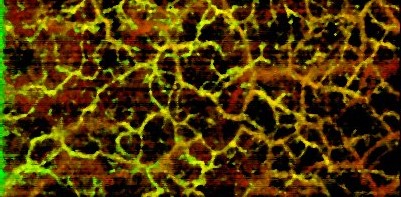

Better roll-off performance and greater camera sensitivity enables visualization of deep vasculature in the dermis.

OCT angiography scans captured with the Cobra-S 800 exhibit reduced motion artifacts due to the high speed of imaging, in addition to high resolution.